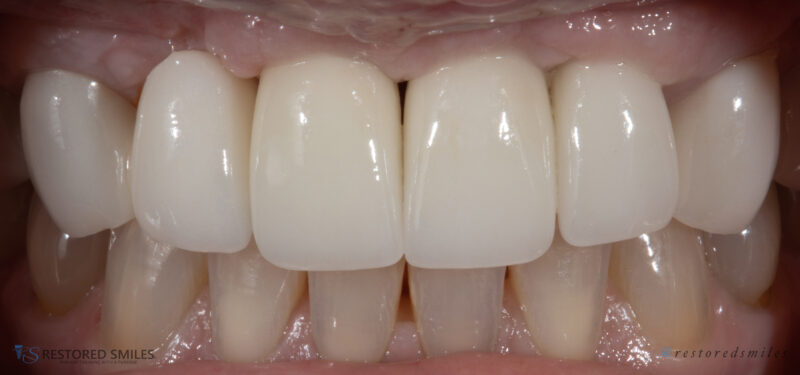

• I’m a big fan of placing immediate implants when indicated. However, with this full arch case this patient had extreme buccal and facial undercuts which prevented immediate implant placement. 6cc’s of bone were used to graft a fair amount of the upper right and upper left quadrant using CGF protocols. 5 to 6 months later we have beautiful,…

Read more